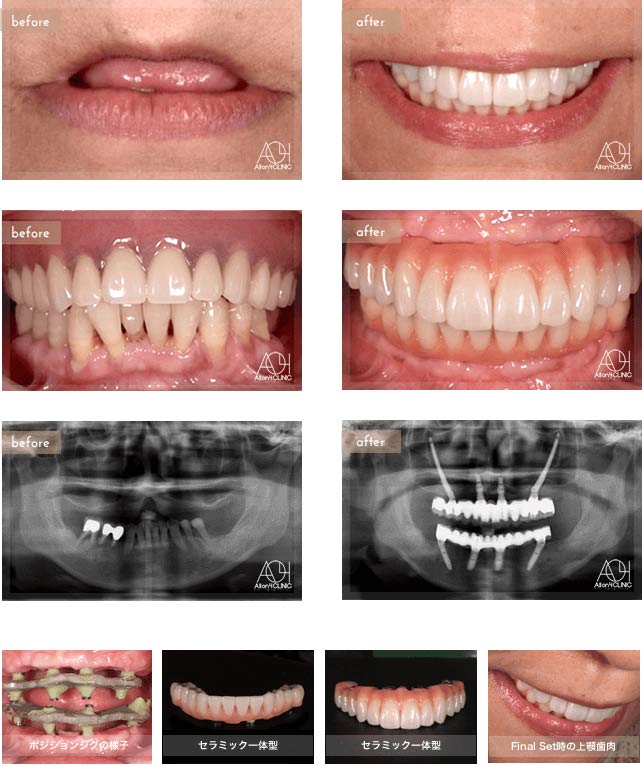

Treatment : All-on-4 non gum

- Upper All-on-4

- Lower implant

Age : 42 Sex : 女 Y.R

| 主訴 | 歯がボロボロなのは分かっているが、時間的な余裕が無いことと歯科に対する恐怖心から、悪いままの状態を放置してしまった。人前でおもいっきり笑いたいので意を決して来院。 |

| 治療内容 | ガイデッドサージェリーにてインプラント埋入。歯槽骨が残っていたため歯冠形態のみ(ガム無し)の補綴 |

| 治療費(総額) | ¥3,500,000(税抜) 『モニター割引適用』 |

| リスク | 治療後の口腔管理が不適切な場合、埋入したインプラント周囲に感染・炎症を起こし、脱落する可能性がございます。 |